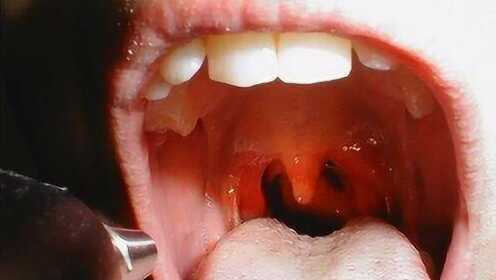

慢性咽炎是一種常見(jiàn)的喉部疾病,主要表現(xiàn)為咽部不適、干燥、瘙癢、疼痛等癥狀,由于長(zhǎng)期受到刺激或感染,咽部黏膜出現(xiàn)慢性炎癥表現(xiàn),慢性咽炎雖然不是嚴(yán)重疾病,但癥狀反復(fù)發(fā)作,嚴(yán)重影響患者的生活質(zhì)量。

在互聯(lián)網(wǎng)上,有關(guān)慢性咽炎三天斷根的信息屢見(jiàn)不鮮,這些宣傳往往聲稱(chēng)采用某種神秘的方法或特效藥物,能在短時(shí)間內(nèi)徹底治愈慢性咽炎,這些宣傳的真實(shí)性有待考證。